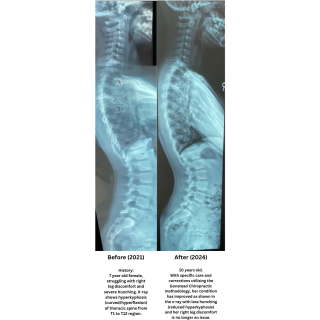

The Gonstead chiropractor goes beyond what many chiropractors consider a spinal assessment by conducting a thorough analysis of the spine using very specific criteria to detect the presence of the vertebral subluxation.